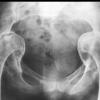

(三)X線檢查:腸道鋇劑檢查有助於病損範圍與性質的確定。但徵象無特異性。鋇劑灌腸示結腸黏膜呈細小的鋸齒樣邊緣,皺壁不規則,腸壁僵硬或痙攣。有時可見腸段狹窄、潰瘍和瘺管形成。少數潰瘍邊緣的黏膜可隆起,其X線征酷似癌腫,其鑑別點是病變段與正常腸段間逐漸移行而無截然的分界限,與癌腫不同。乙狀結腸位置較低並摺疊成角。應從不同角度攝片對鑑別病變性質有重要意義。